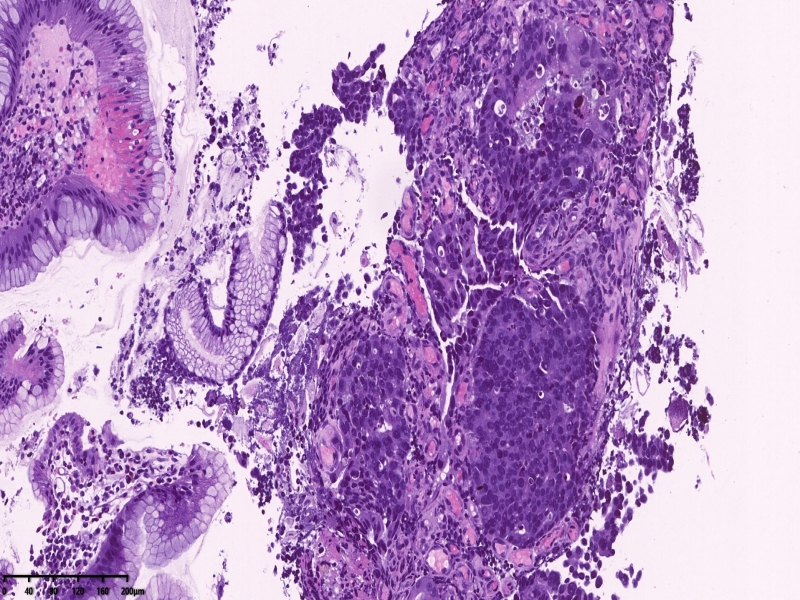

镜下所见:胃粘膜组织数块,炎症背景,其中3块固有层内可见细胞团,瘤细胞排列呈条索状迂回后呈巢状,巢的边缘瘤细胞呈栅栏状。细胞形态似柱状。

第一感觉考虑神经内分泌肿瘤?会诊考虑低分化腺癌。以前也遇到一个类似病例,贲门口占位,初步考虑神经内分泌肿瘤,但是神经内分泌标记均为阴性,最后考虑低分化腺癌。